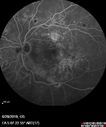

80 year old man has been told that he has swelling in the retina and some bleeding. His vision is pretty good. You asked him to come here for a checkup and possible treatment. He did have laser in both eyes about 6 years ago. He does not want laser VA OD: Dcc20/40-1 NccJ3 VA OS: Dcc20/40-1 NccJ2

Diabetic Macular Edema with Exudates486 viewsPatient did not want injection therapy and did well with laser00000